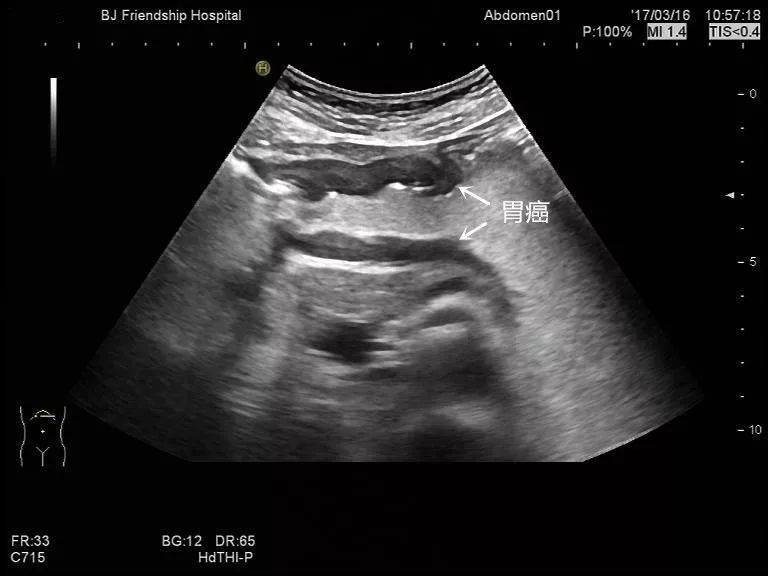

胃体部胃癌: